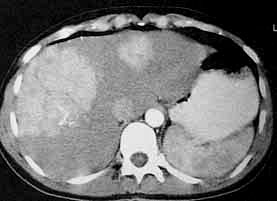

患者女,39岁,无相关症状.平扫显示肝内两个孤立的低密度灶.

增强扫描延迟20秒显示两个明显强化的病灶,内有中心瘢痕.

延迟2分钟显示病灶和肝实质密度一致.

5个月后复查显示两个病灶没有变化.

(病例经腹腔镜证实为肝局灶结节增生)